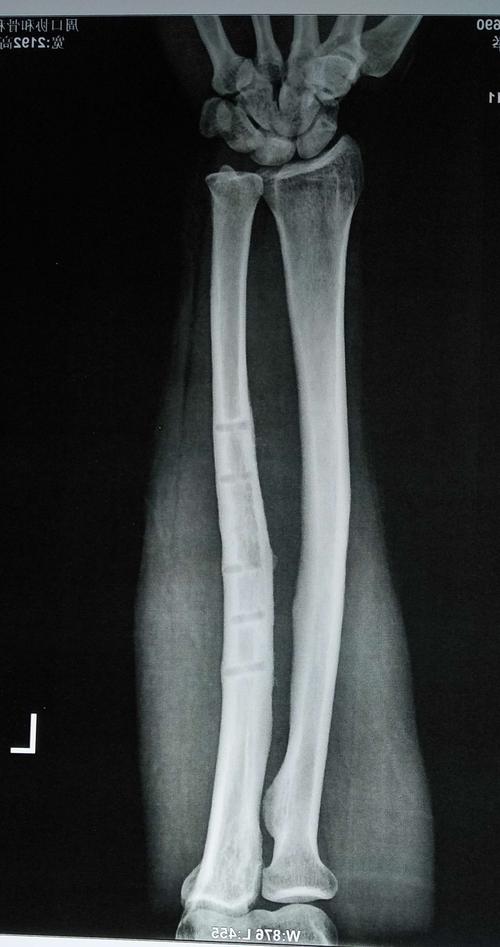

骨折愈合图片对比x光,骨折愈合图片x光

术后x线片提示:原骨折处愈合良好,钢板内固定完全取出.

骨折愈合图片x光

小腿骨折愈合图片